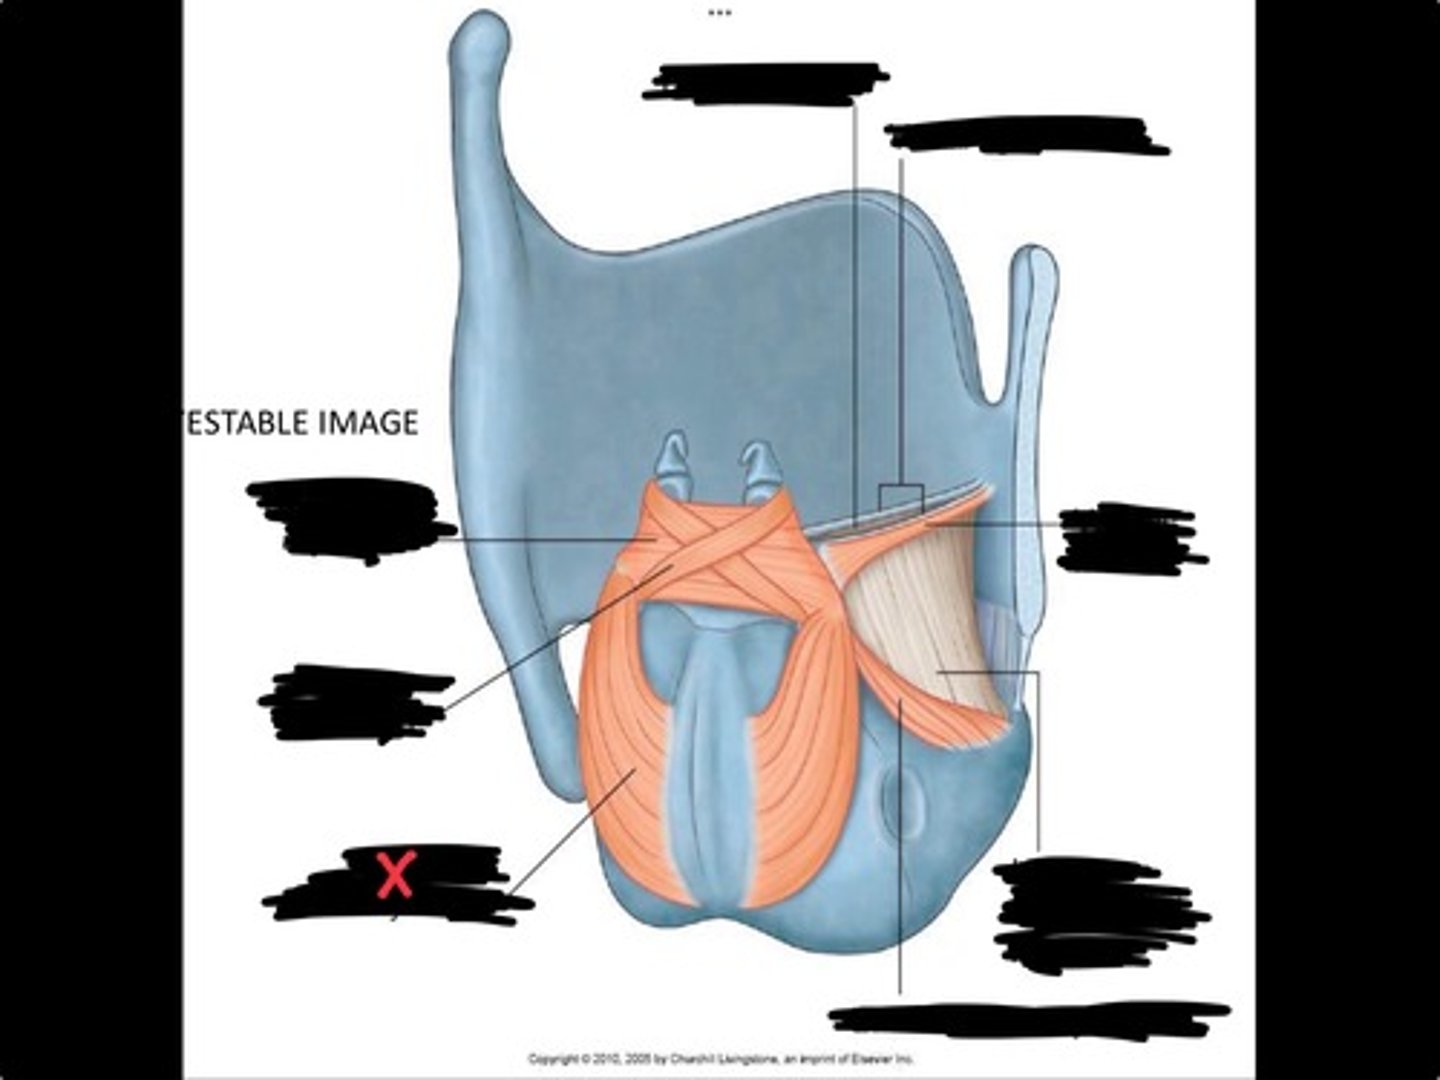

Vocal process of arytenoid

Conus elasticus

Vestibular ligament

Quadrangular membrane

Epiglottis

vocal ligament

Aryepiglottic ligament

Muscular process of arytenoid

Corniculate cartilage

Posterior crico arytenoid

oblique arytenoid

transverse artyenoid

Rima glottidis

Vocal ligament

Vocalis muscle

Lateral cricothyroid ligament

Lateral cricoartenoid